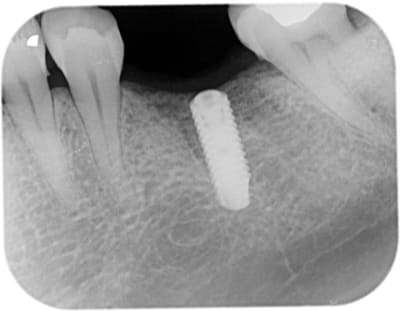

comme ce petit cas

la 2ème radio est prise 18 mois après la 1ère

PS pour Gulguch c'est bien un implant de 6 mm de diamètre en distal et pourtant pas la moindre perte osseuse...

si tu regarde bien la radio il y a une "esquille" (tarte ou /et ciment) entre les deux piliers et mauvais "joint" donc il ne faut peut être pas accuser l'implant dans ce cas là.

je voulais justement signifier l'inverse cad malgré des "soucis" de tartre et joint le niveau osseux est au dessus de l'implant